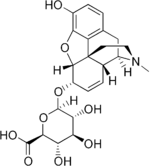

- Esters of morphine opiates: slightly chemically altered but more natural than the semi-synthetics, as most are morphine prodrugs, diacetylmorphine (morphine diacetate; heroin), nicomorphine (morphine dinicotinate), dipropanoylmorphine (morphine dipropionate), desomorphine, acetylpropionylmorphine, dibenzoylmorphine, diacetyldihydromorphine;[261][262]